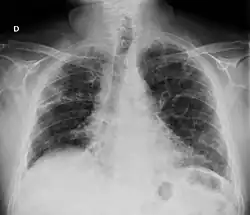

- Pulmón

- La fibrosis pulmonar es una complicación reconocida de la artritis reumatoide[57][58][59] y también puede ser una consecuencia de algunos tratamientos —por ejemplo del metotrexate y leflunomida—.[60] El síndrome de Caplan describe la presencia de nódulos reumatoideos pulmonares en pacientes con artritis reumatoide y exposición al polvo de sílice o carbón. Los derrames pleurales no son raros en el contexto de la artritis reumatoide y obligan a descartar otras posibles causas. Estas alteraciones pulmonares, además de la bronquiolitis obliterante se denominan globalmente enfermedad pulmonar reumatoide, estimándose que al menos una cuarta parte de los pacientes con artritis reumatoide desarrollan afectación pulmonar.[61][62]